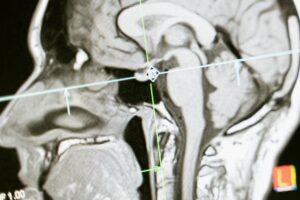

Brain scans revealing patterns your mind didn’t know it had.

With great access comes great responsibility. As brain monitoring becomes more precise, society faces philosophical and regulatory dilemmas. Can a company use your brain data to sell products or influence decisions? Could insurance companies adjust premiums based on neural risk profiles? Science fiction is fast becoming science fact, and the moral calculus is complicated, messy, and thrilling.